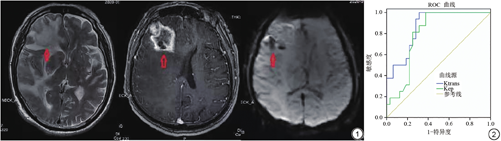

不同BG病理分级者Kep、Vp比较,差异无统计学意义(P>0.05);BG病理分级Ⅱ级者Ktrans及Ve明显低于Ⅲ级、Ⅳ级者(P<0.05),但Ⅲ级与Ⅳ级者间Ktrans、Ve比较,差异无统计学意义(P>0.05),见表1,典型病例分析见图1。

ROC曲线分析显示,Ktrans、Ve均对BG病理Ⅳ级具有一定诊断价值(P<0.05),见表2、图2。